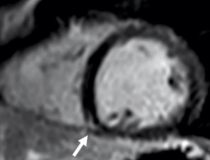

This photo gallery shows the variety of radiological presentations of COVID-19 (SARS-CoV-2) in medical imaging, including computed tomography (CT), radiograph X-rays, ultrasound, echocardiograms and magnetic resonance imaging (MRI). The radiology images show examples of typical COVID pneumonia in the lungs and the numerous complications the virus causes in the body in multiple organs, including the brain, kidneys, heart, abdomen and vascular system.

Ultrasound, especially hand-held ultrasound imaging devices, have become a primary imaging modality for novel coronavirus because of the ease to bag the device and sterilize it after use. CT and mobile X-ray systems are also used as front-line imaging systems for COVID-positive or suspected COVID patients.